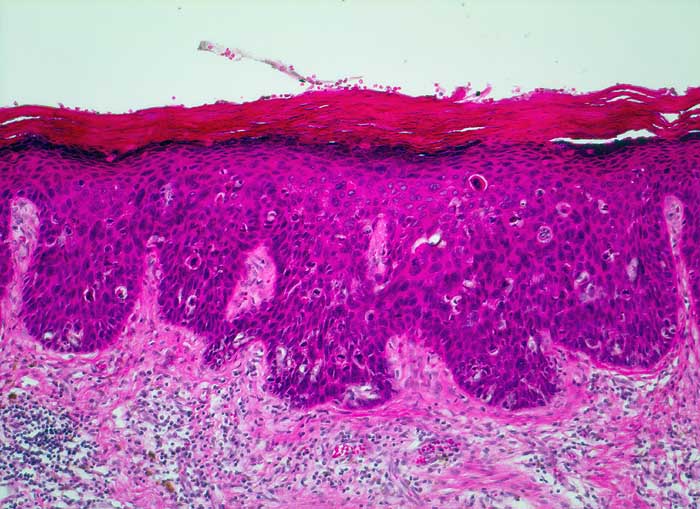

PathoPic – image database / PathoPic ID 5540 - Carcinoma in situ (VIN III)

Carcinoma in situ (VIN III)

Vulva

Die Zellen des Plattenepithels zeigen in der gesamten Breite ausgeprägte Kernatypien. Zahlreiche suprabasale Mitosen. Hyperkeratose und Dyskeratose. Invasives Wachstum ist nicht erkennbar. Die Basalmembran ist auf der gesamten Länge erhalten.

Hautulkus im Bereich des Carcinoma in situ.

Histologie

100